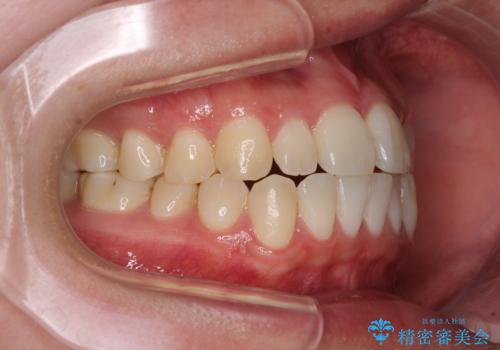

すきっ歯とオープンバイトをインビザラインで改善

- 前歯の上下スペースと前歯の隙間を気にして来院された患者様です。

インビザラインにより上下の前歯の隙間を閉じていくこととしました。

上下の隙間に舌が入り込むことが、すきっ歯やオープンバイトの原因であったため、舌の筋肉のトレーニングも並行して行い、後戻りの抑制を図りました。